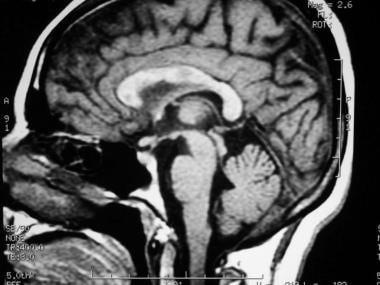

“At the 2025 Annual Meeting of the American Academy of Neurology, I am looking forward to hearing about the new diagnostic criteria for relapsing-remitting MS. The McDonald criteria have been updated in 2024. This update includes a new application of MRI techniques that makes them more specific and more sensitive for the diagnosis of relapsing-remitting MS.”

Dr Bhargava previews the 2025 Annual Meeting of the American Academy of Neurology (AAN), where the updated diagnostic criteria for RRMS will be discussed, with a focus on new MRI techniques that improve specificity and sensitivity. The meeting will also address the impact of social determinants of health on MS, along with updates on biomarkers for diagnosis and prognosis, and new treatment options. Additionally, there will be insights into how diet can be optimized to improve disease outcomes for patients with MS.